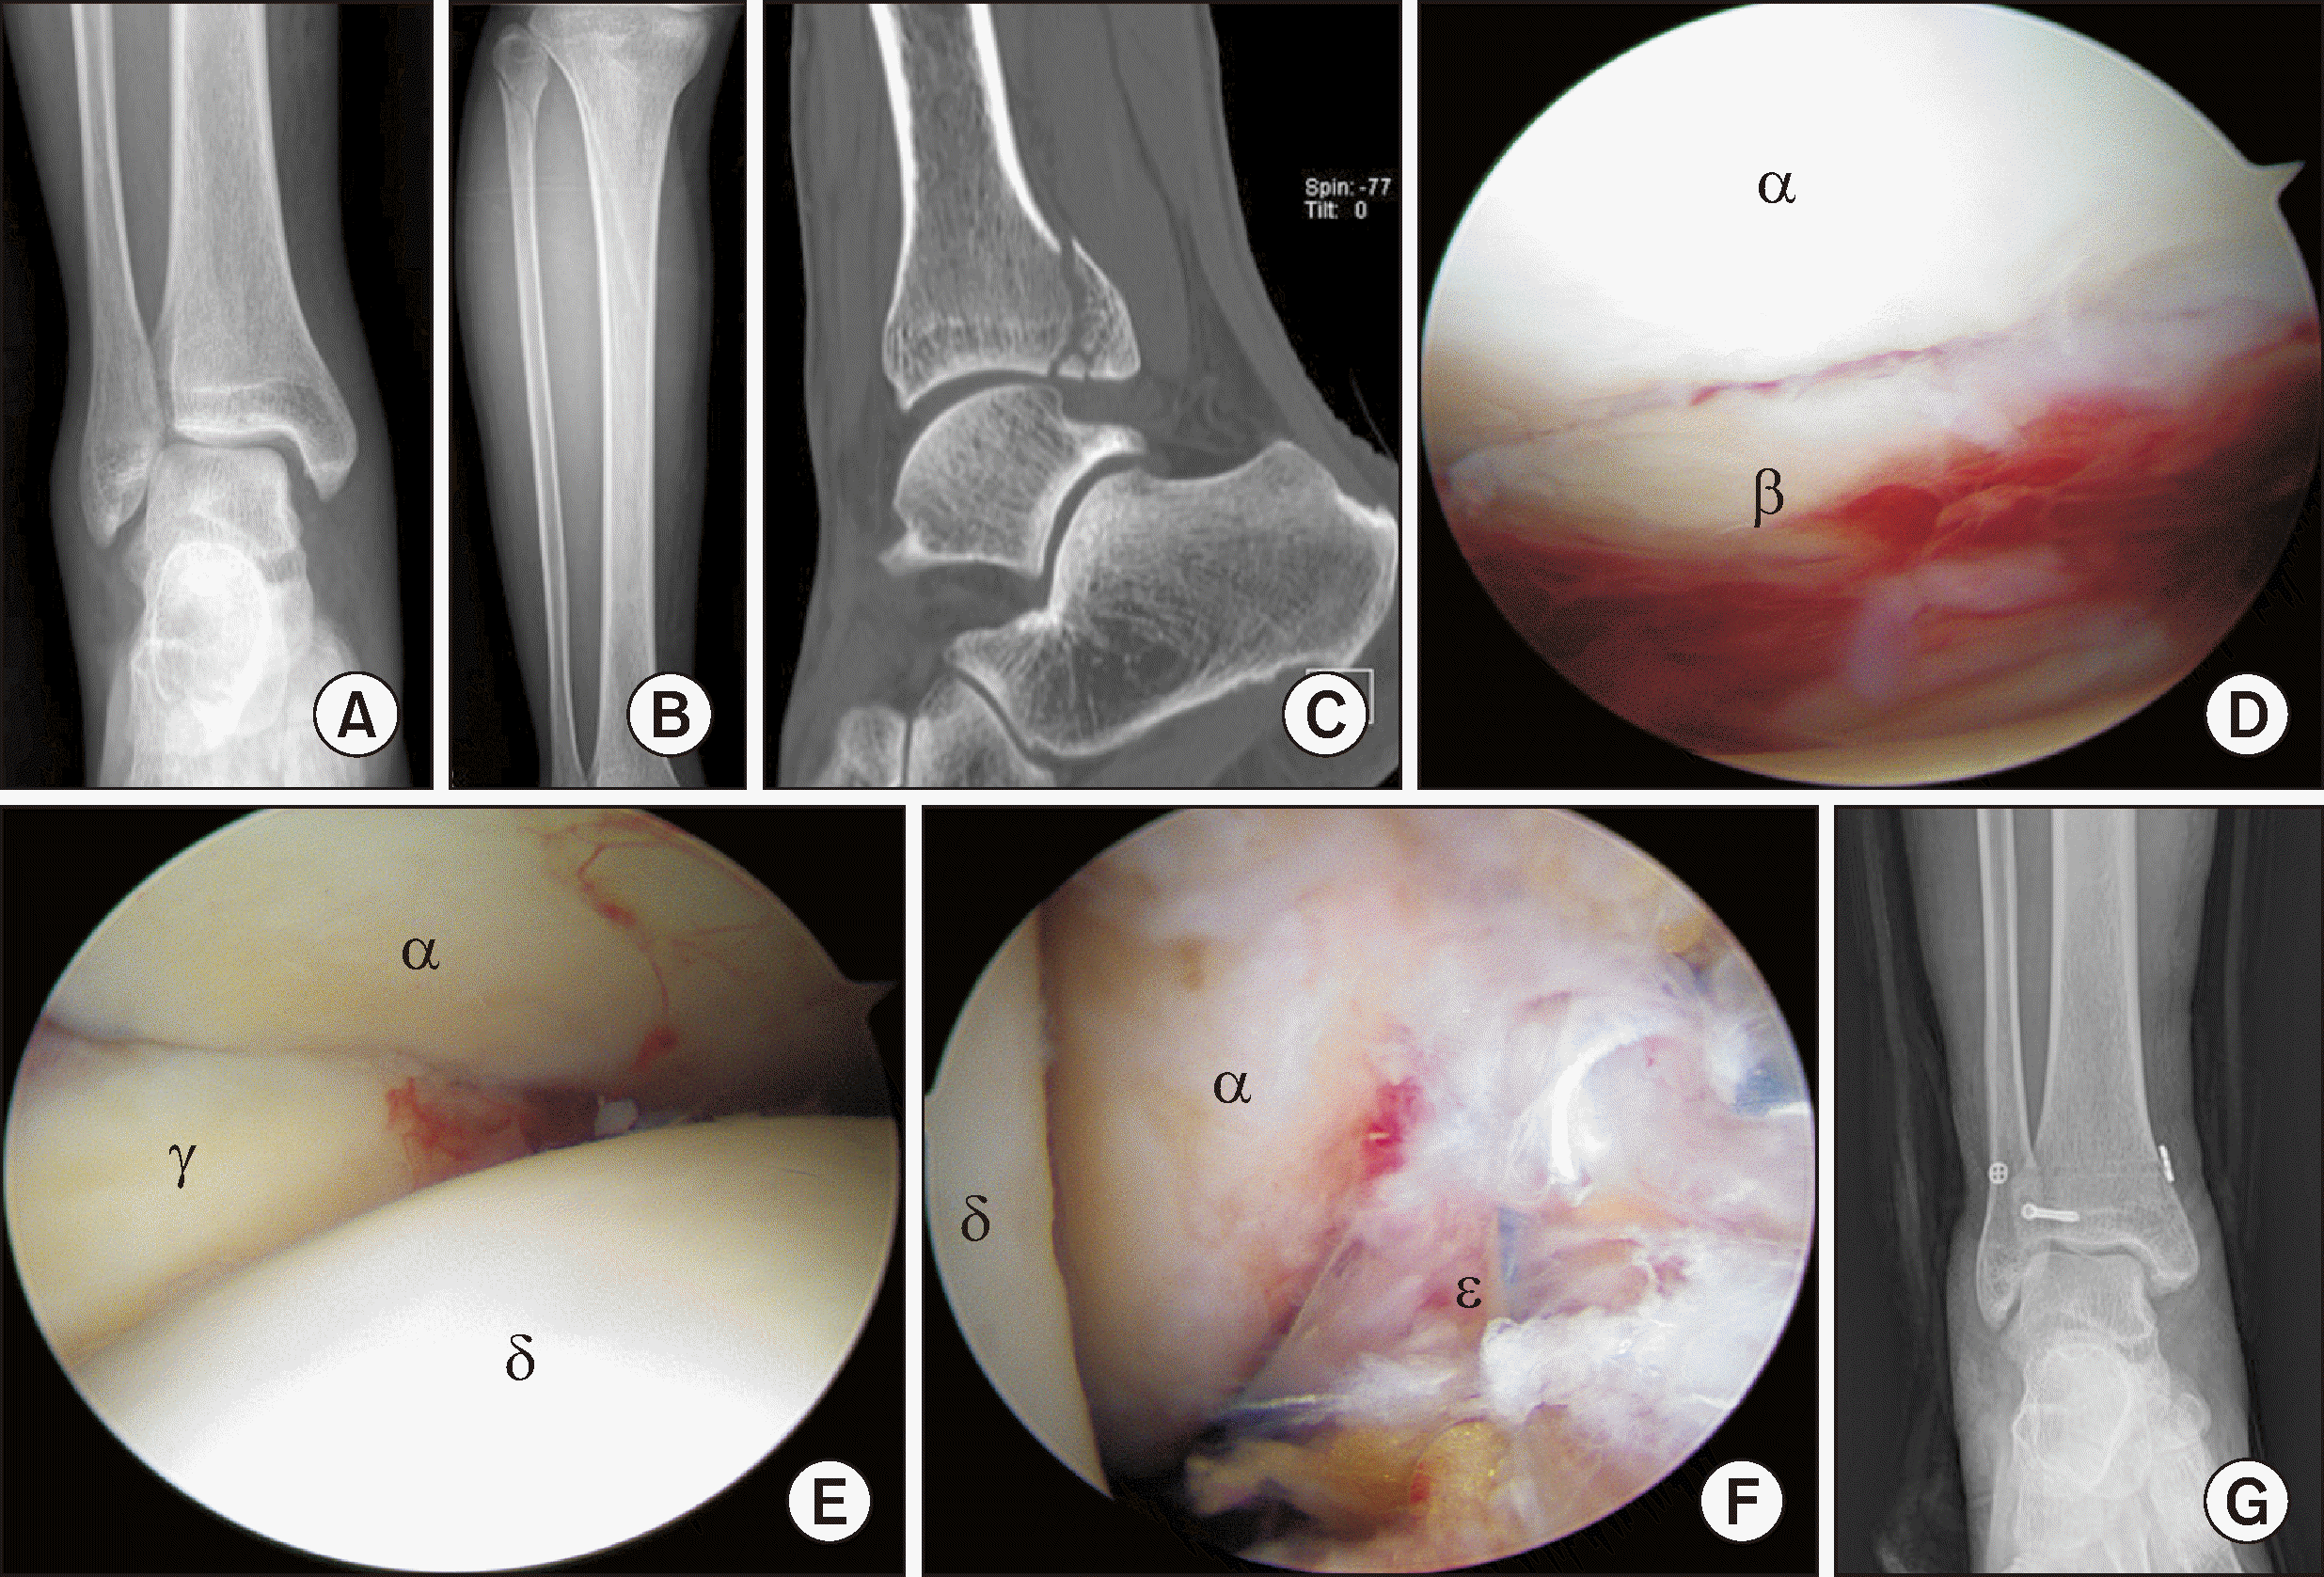

Figure 6

The arthroscopic findings show the medial malleolar fracture before (A) and after (B) arthroscopic reduction. αTibia, βTalus, γfractured medial malleolus.

Figure 7

(A) The sagittal CT image shows a displaced posterior malleolar fracture. (B, C) The arthroscopic findings show the posterior malleolar fracture before (B) and after (C) arthroscopic reduction. αTibia, βTalus, γFibula, δfractured posterior malleolus.

Figure 8

(A) The CT scan shows a pediatric Tillaux fracture. The arthroscopic findings show the pediatric Tillaux fracture before (B) and after (C) arthroscopic reduction. (D) After arthroscopic reduction, percutaneous fixation with screw and Kirschner wire was performed. αTibia, βTalus, γTillaux fracture fragment.

Figure 9

Plain radiographs (A, B) and CT scan (C) show widening of the medial clear space, proximal fibular fracture, and posterior malleolar fracture, indicating a Maisonneuve fracture. The arthroscopic findings show reduced posterior malleolar fracture (D), syndesmosis injury (E) and repaired deltoid ligament (F). (G) Plain radiograph shows percutaneous fixation of posterior malleolar fracture with screw and syndesmosis fixation with TightRope. αTibia, βPosterior malleolar fracture, γFibula, δTalus, eRepaired deltoid ligament.